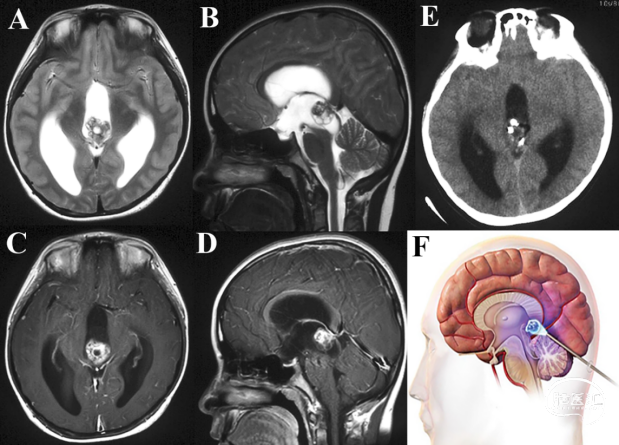

中国医学科学院肿瘤医院万经海教授:内镜手术完整切除松果体区畸胎瘤

作者:左赋兴 万经海

患儿9岁,男性,两周前突发剧烈头痛呕吐晕厥,当地医院考虑松果体区占位病变致梗阻性脑积水。患儿后于我院就诊,查体见双眼上视不能。头颅MRI明确三脑室后部混杂信号病变,中脑顶盖和四叠体受压下移,增强扫描见肿瘤显著不均匀强化,与大脑内静脉和Galen复合体关系密切;头颅CT提示肿瘤密度不均伴钙化,幕上脑室系统显著扩大。